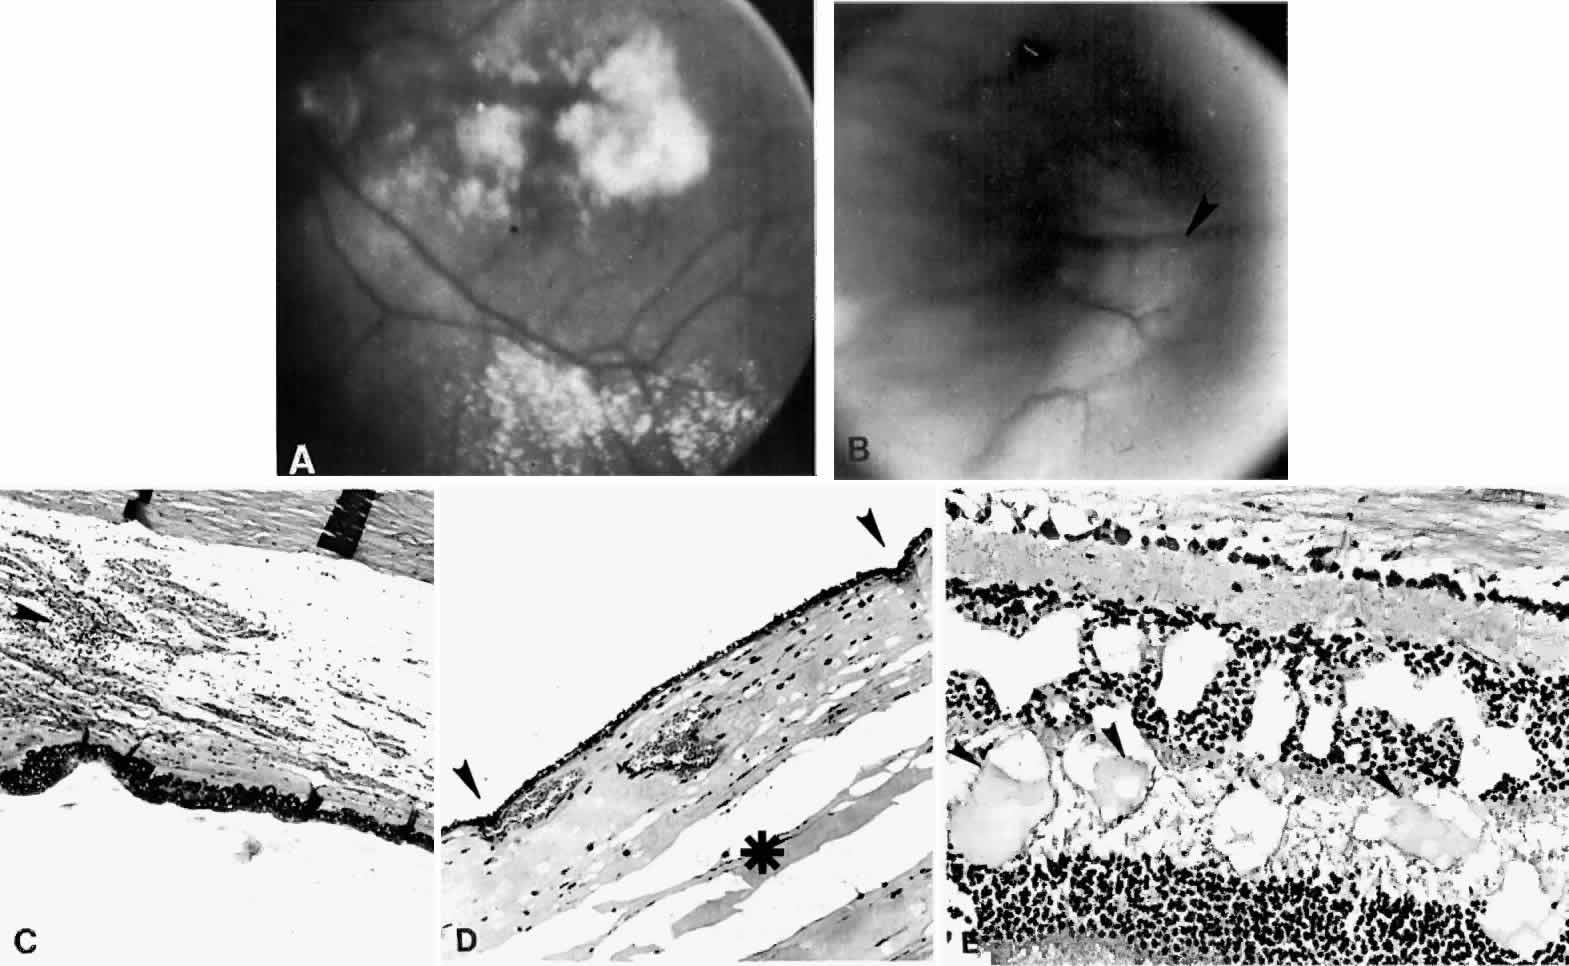

The pathogenesis of uveal effusion syndrome (Fig. 18), also referred to as idiopathic ciliochoroidal effusion, has not been clearly defined, but it is now thought to be primarily due to an abnormality in scleral thickness.92 It is usually unassociated with any other ocular or systemic abnormalities and occurs in the noninflamed eyes of middle-aged men as an insidious, progressive, usually bilateral non-rhegmatogenous retinal detachment with shifting fluid. This detachment can occur before there is any detectable ciliochoroidal elevation. Other findings include flat peripheral ciliochoroidal effusion, scattered retinal exudates, and localized areas of RPE hypertrophy and hyperplasia (“leopard spots”) (see Fig. 1).12,13,69,70,92,94 Evidence of uveal, retinal, or vitreous inflammation is minor or absent (see Fig. 18).

The literature does not clearly distinguish between uveal effusion syndrome and idiopathic ciliochoroidal effusion.9,65 They may most likely represent the same entity. In fact, findings similar to those for uveal effusion syndrome have been described in eyes with idiopathic ciliochoroidal effusion (Figs. 19B and 20C and D). An idiopathic ciliochoroidal effusion, however, is considered clinically and pathogenetically different from an effusion in a nanophthalmic eye, which is small and chronically hypotonous.89

Fig. 19. A. A ciliochoroidal effusion (asterisk) mistaken for a malignant melanoma and associated with moderately severe panuveitis. A secondary serous retinal detachment (arrowhead) and moderately thickened sclera are evident (H & E, × 15). B. Equatorial choroid with effusion and moderate infiltration of chronic inflammatory cells. Small nodules of proliferated retinal pigment epithelium (arrowheads) and subretinal proteinaceous material (arrow) are shown (H & E, × 80). C. Moderately intense infiltration of plasma cells and some lymphocytes (H & E, × 530). (Courtesy of the Armed Forces Institute of Pathology, Washington, DC)

Fig. 20. A 61-year-old man presented with a 10-day history of decreasing vision in the left eye.96 Examination disclosed a vision of hand motions, an irregularly shallow anterior chamber, closure of the angle, and an intraocular pressure of 45 mmHg. The ora serrata was visible without scleral depression. Ophthalmoscopic examination disclosed two large areas of solid-appearing lesions of the pars plana and anterior choroid (situated superonasally and inferotemporally), detachment of the retina, and a diffuse pigmentary disturbance, which was linear in some areas. Transscleral transillumination disclosed that areas of solid choroidal lesions lit up when viewed through the pupil. Radioactive phosphorus uptake was 16% at 1 hour, 18% at 24 hours, and 44% at 72 hours. The eye was enucleated because of the suspicion of a malignant melanoma. A. An extensive ciliochoroidal effusion (asterisks) showing mild diffuse and marked focal (arrowhead) infiltration of lymphocytes. The equatorial sclera is markedly thickened, and there is a large serous detachment of the retina (H & E, × 17). B. Edematous choroid with a large aggregate of lymphocytes (H & E, × 100). C. The equatorial area shows a thickened sclera, an edematous choroid with diffuse and marked focal aggregates of lymphocytes, localized area of retinal pigment epithelial hypertrophy and hyperplasia (arrowheads), slight folds in the retinal pigment epithelium and inner aspect of the choroid (arrows), and proteinaceous material (asterisk) in the subretinal space (H & E, × 40). D. A choroidal effusion with overlying proliferation of retinal pigment epithelium in nodular and linear configurations. Proteinaceous material is present in some areas in or beneath the retinal pigment epithelium (arrowheads) (H & E, × 180).

Histopathologically, there is a variable lymphocytic infiltrate in the ciliary body and choroid (see Figs. 19 and 20; Fig. 21).96

Fig. 21. A. Retinal exudates situated inferotemporally in the left eye of a 46-year-old woman with idiopathic ciliochoroidal effusion mistaken for a malignant melanoma and associated histopathologically with mild uveitis. Exudate in the macular area had a yellowish-orange appearance. B. Appearance of “solid-detachment” ciliochoroidal effusion with a meridionally oriented fold (arrowhead). C. Pars plana area with faintly stained proteinaceous material separating the smooth muscle fibers and tangentially oriented fibers associated with a mild lymphocytic infiltration (arrowhead) (H & E, × 50). D. Effusion of the choroid (asterisk) near the equator by a more densely stained proteinaceous material with a very light scattering of lymphocytes. Circumferentially oriented folds (arrowheads) involving the retinal pigment epithelium and inner aspect of the choroid are evident (H & E, × 135). E. Edema and cystic changes in the retina below the fovea. Most cysts in the inner nuclear layer have no staining material present, but those in the outer plexiform layer have a lightly staining proteinaceous material (arrowheads) (H & E, × 215).